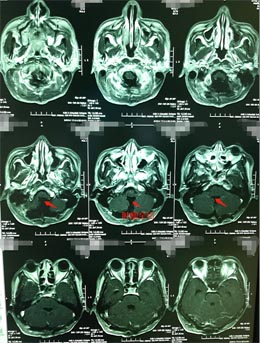

入住广东三九脑科医院神经外五科后,由医院副院长、神经外五科主任鲁明主刀,在全麻下行脑干背侧-四脑室肿瘤切除术,术中全切肿瘤,术后陈先生神志清醒,遵嘱活动。术后病理提示:室管膜瘤II级。

室管膜瘤根据其恶性程度和侵袭性分为4级,从1至4级,恶性度逐级递增,因为此肿瘤多位于脑室内,有一定的生长空间,故疾病早期症状不明显,因此也很难做到早期发现。术中在高倍显微镜将肿瘤从脑干分离,手术难度、风险大,容易损伤脑干导致昏迷不醒,如果能尽可能的进行全部切除肿瘤,病人的生存时间会更长。本手术成功完全切除肿瘤,没有留下后遗症。

▲手术后